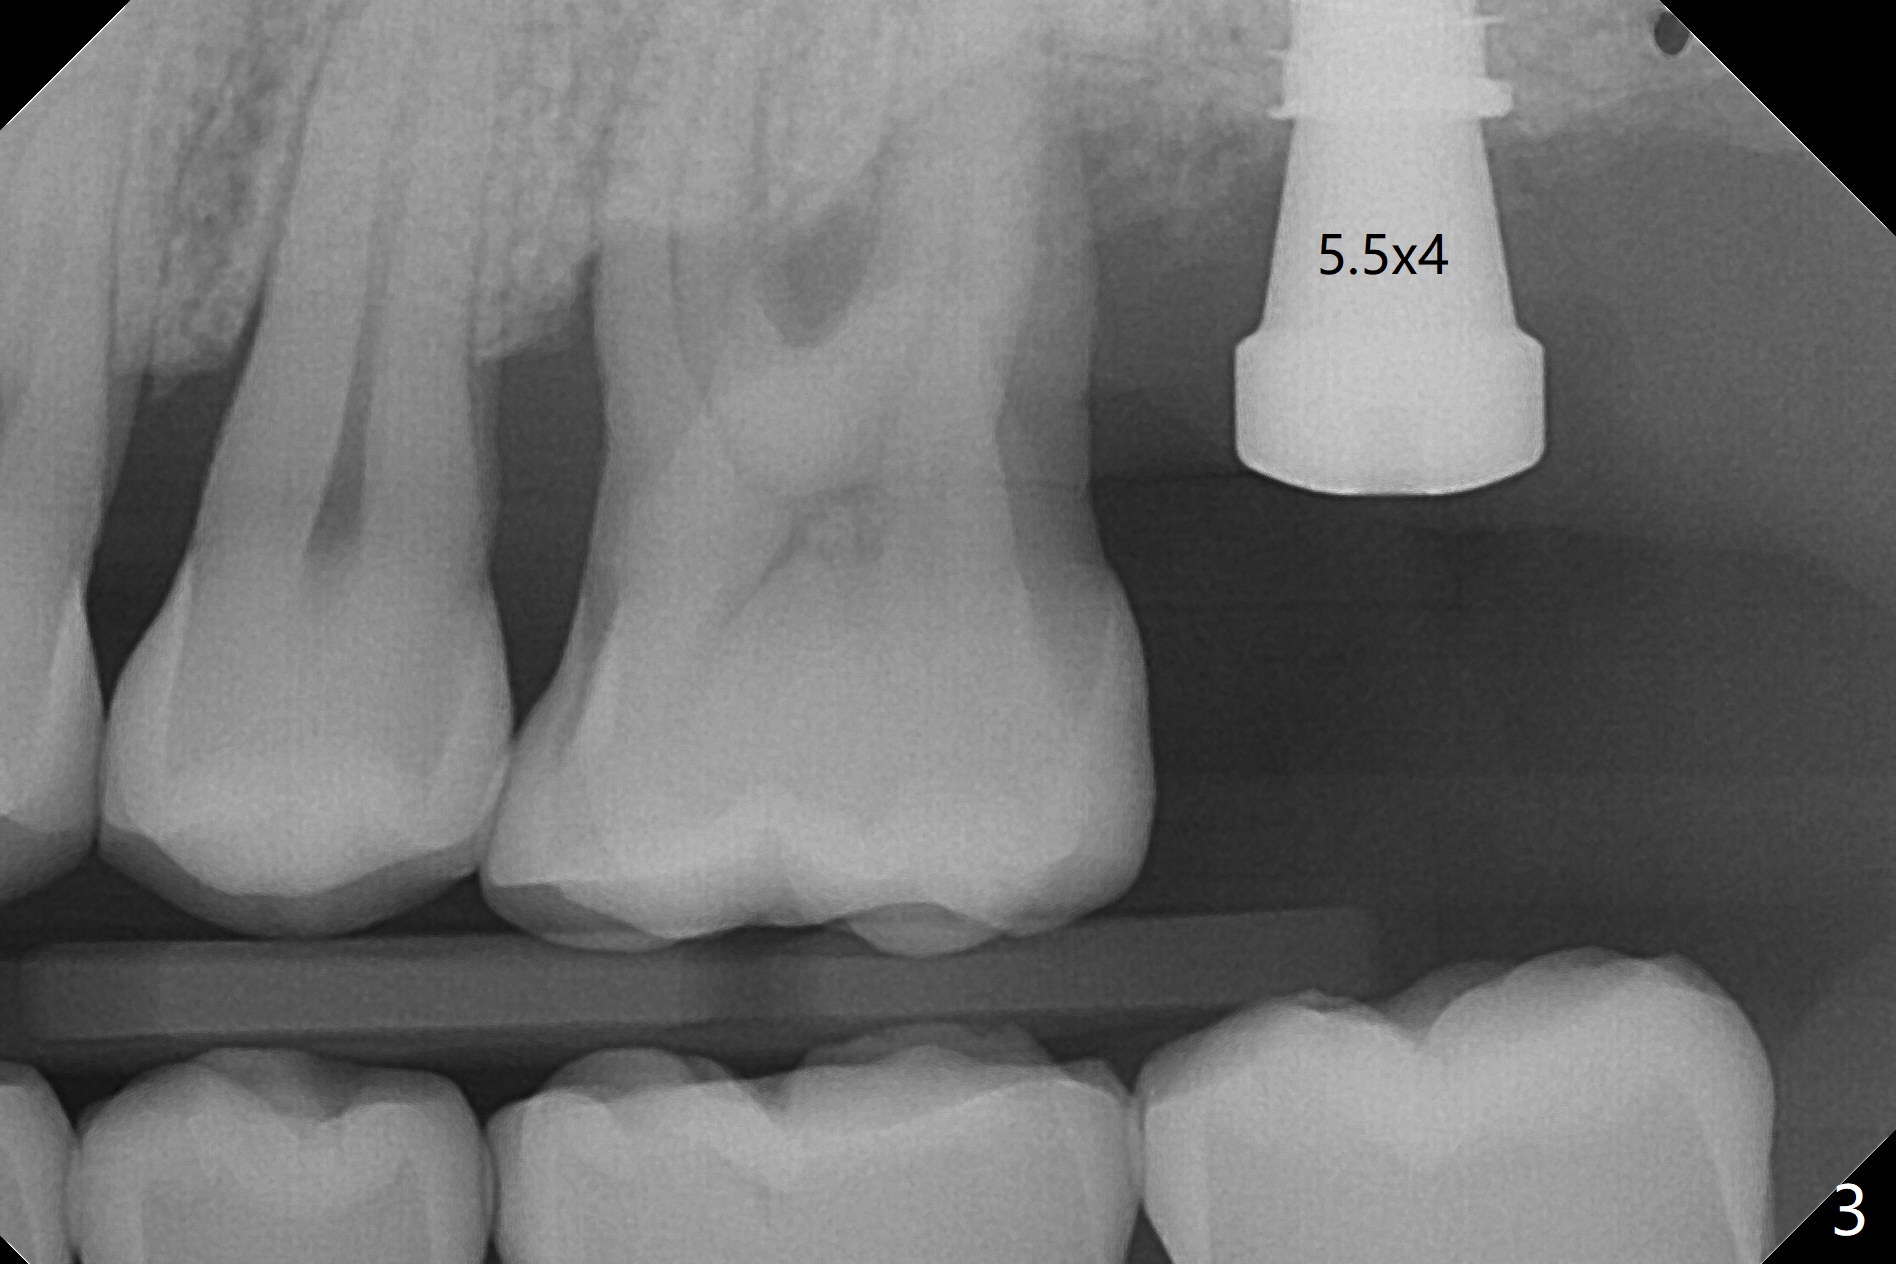

cartridge),植入短小植体(4.5x7毫米,原定(5x8.5毫米)图二),由于稳定性好,使用5.5毫米profile钻头后,放置5.5x4毫米愈合基台(图三)。术后病人没有什么上颌窦不适和分泌物。估计Novo